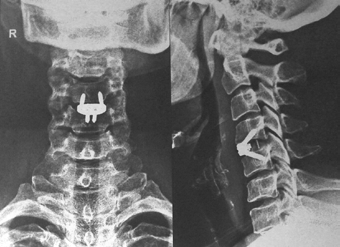

c0 c1 c2 fixation

c1 c2